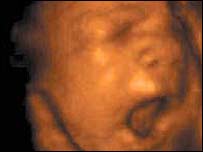

पंजाब में कुएँ में मिले कन्या भ्रूणों की ख़बर ने झकझोर कर रख दिया और बरबस ईरान की याद आ गई.

भारत में भ्रूण हत्या के मामलों में कमी नहीं